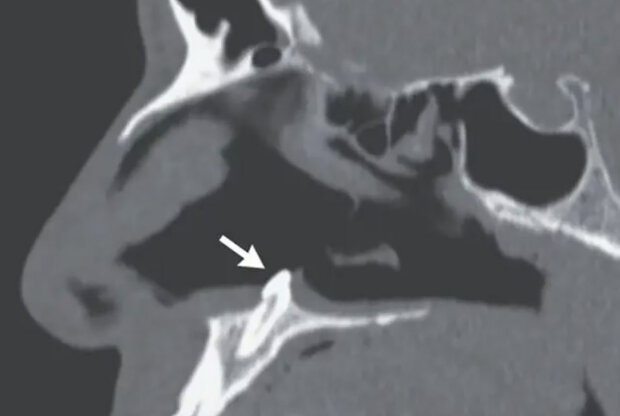

Lékaři pak provedli endoskopii a našli v pravé nosní dírce bílý předmět, který byl později identifikován jako ektopický, tedy zub, který vyrostl na nesprávném místě.

Zub byl 1,4 centimetru dlouhý a byl odstraněn během otolaryngologické operace. Lékaři uvedli, že tři měsíce po zásahu už pacient neměl problémy s dýcháním.